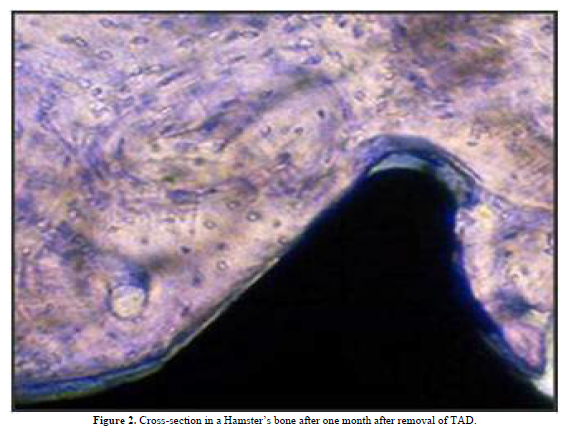

The question about TADs safety has been a concern at their advent; however, the histologic studies have pointed out their reliability pertinent to the adjacent structures, Figures (1,2).